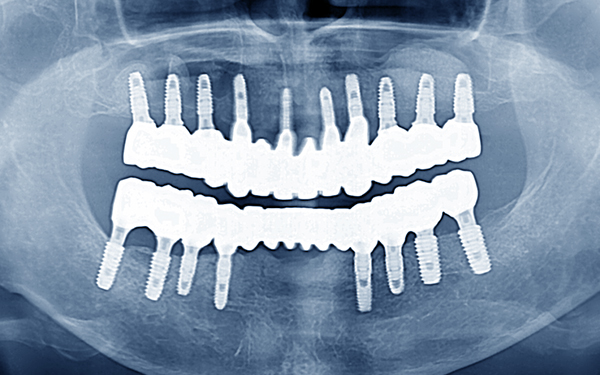

전체 임플란트치료는,

심한 충치, 치주질환, 사고 등의 이유로 개인의 모든 치아가 상실된

경우, 본래의 모습을 회복하기 위해 20개 정도의 임플란트를 식립하는

큰 치료입니다. 보통 치아가 하나도 없는 경우는 잇몸도 좋지 않고,

씹는 습관도 불안정한 경우가 많습니다.